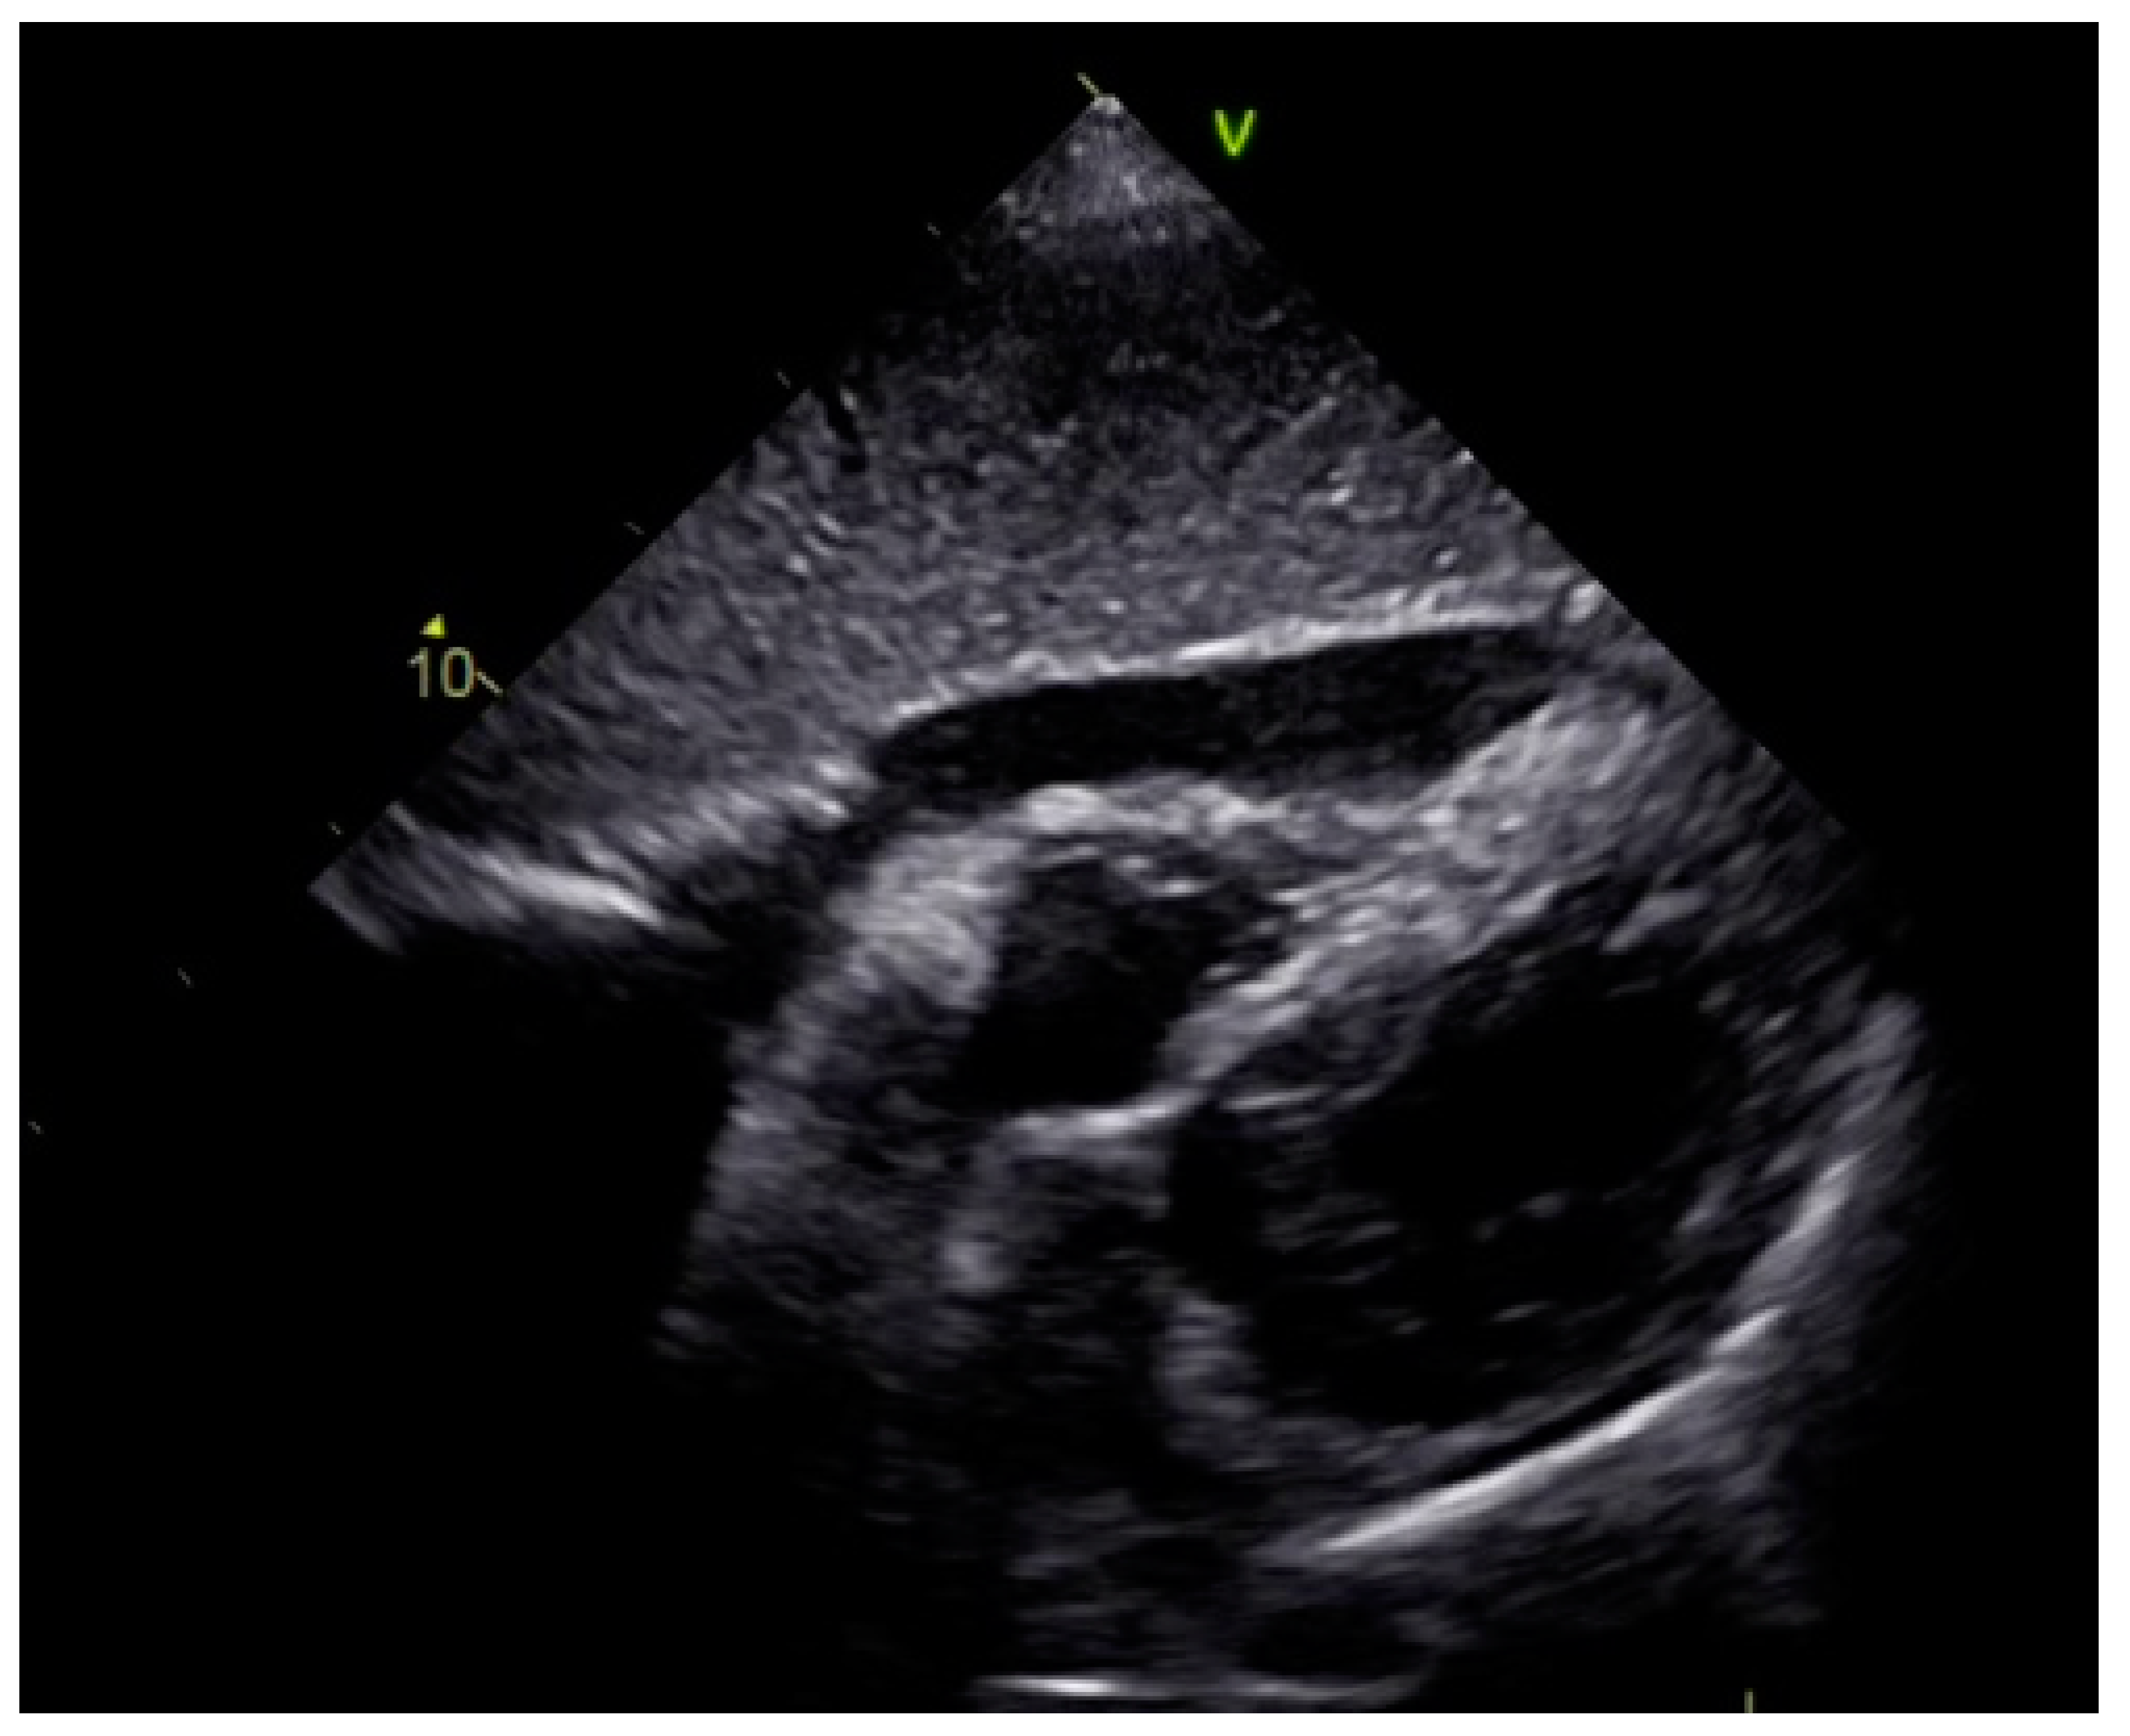

As a result, the patient was referred to a specialized medical institution. Upon admission, the patient was conscious, confused, hypotensive (TA 80/50 mmHg), with a heart rate of about 110/min, and showing clinical signs of hypoperfusion and cardiogenic shock, Killip IV. The medical staff administered sedation, inserted an endotracheal tube, and placed her on invasive mechanical ventilation. The patient was given crystalline solutions, inotrope, and vasopressor medication. An urgent echocardiographic examination was performed due to a rough systolic murmur over the precordium. It revealed akinesia of all medioapical segments of the left ventricle and akinesia basally inferior, where the myocardium was fibrously altered. Other hyperkinetic basal segments formed a dynamic obstruction of the left ventricular outflow tract (LVOTO) with turbulent flow and moderate mitral regurgitation (Figure 2 and Figure 3). The maximum gradient above the LVOT was 160 mmHg (Figure 4). The aortic valve area was 1.8 cm2 (Figure 5). The ejection fraction of the left ventricle (LVEF) was estimated to be 25%. The examination also revealed pericardial effusion with separation between pericardial layers along the right ventricle and atrium of up to 1.2 cm, but without any signs of tamponade.

Figure 2.

Echocardiography registered basal hyperkinetic segments of the left ventricle and formed a dynamic obstruction of the left ventricular outflow tract (a—LVOT, b—cuspi anterioris valvulae mitralis, c—aortic valve).